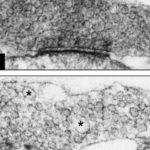

Immagine: la crescita assonale nelle cellule staminali neurali umane è stata stimolata in presenza di mielina derivata da scimmie o ratti. Credito: GHD Poplawski et al., Science Translational Medicine (2018).

Ma in un nuovo articolo, pubblicato sul numero online di Science Translational Medicine del 23 maggio, i ricercatori della San Diego School of Medicine della University of California hanno riferito che la mielina di ratto adulto stimolava effettivamente la crescita assonale nelle cellule del precursore neurale del ratto (NPC) e nelle cellule staminali pluripotenti umane indotte ( cellule staminali neurali (NSCs) acquisite da iPSC).

Il laboratorio di Tuszynski, con colleghi in Germania e Singapore, ha monitorato l’escrescenza dei neuriti da NPC e NSC che crescono su un substrato di mielina in piastre di Petri. I neuriti sono proiezioni dai corpi cellulari dei neuroni, o assoni (che trasportano segnali verso altri neuroni) o dendriti (che ricevono i segnali). In entrambi i casi, i ricercatori hanno scoperto che l’escrescenza aumentava di tre volte.

In studi successivi su ratti con lesioni del midollo spinale, i ricercatori hanno scoperto che NPCs di ratto e NSCs derivati da iPSC umani impiantati nel sito della lesione estendevano un numero maggiore di assoni sia attraverso la materia bianca del sistema nervoso centrale adulto che attraverso la materia grigia e preferenzialmente alla presenza di mielina.